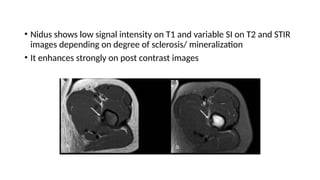

• Nidus shows low signal intensity on T1 and variable SI on T2 and STIR

images depending on degree of sclerosis/ mineralization

• It enhances strongly on post contrast images

• Nidus showslow signal intensity on T1 and variable SI on T2 and STIR images depending on degree of sclerosis/ mineralization • It enhances strongly on post contrast images